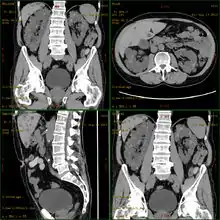

Diagnosis may be suspected from one, some, or all of the following: new onset flank pain or red urine; a positive family history; palpation of enlarged kidneys on physical exam; an incidental finding on abdominal sonogram; or an incidental finding of abnormal kidney function on routine lab work (BUN, serum creatinine, or eGFR). Definitive diagnosis is made by abdominal CT exam.

Polycystic kidney disease can be ascertained via a CT scan of abdomen, as well as, an MRI and ultrasound of the same area.[23] A physical exam/test can reveal enlarged liver, heart murmurs and elevated blood pressure[1]